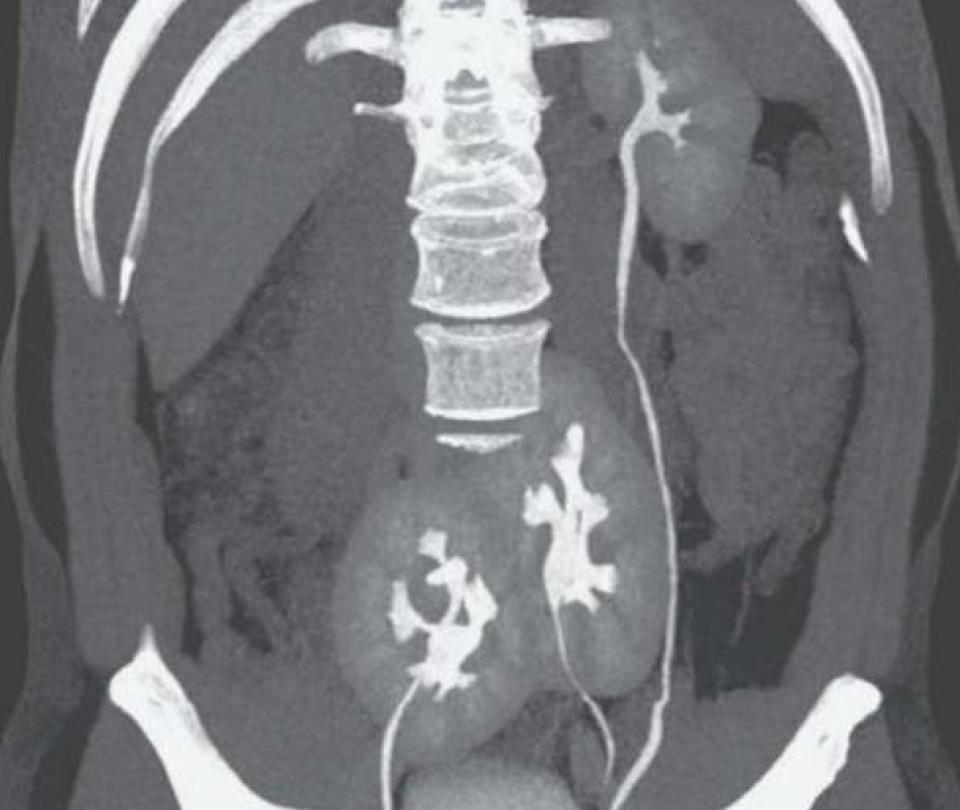

Procedieron, entonces, a realizar una tomografía y se encontraron con el que el paciente tenía tres riñones.

“El riñón izquierdo tenía la apariencia normal, mientras que en el lado derecho tenía dos riñones fusionados”, explicó el diario argentino ‘La Nación’.

Según el informe que publicaron en el medio científico, los tres riñones podrían estar relacionados con una “posible falla congénita que se produjo en el embrión cuando se estaban formando los órganos (…) Por alguna razón desconocida, uno de los futuros riñones se divide en dos”.

“Esta situación se conoce en medicina como riñón supernumerario y es tan poco frecuente que, en los últimos 150 años, solo se han documentado 100 casos”, se agregó.